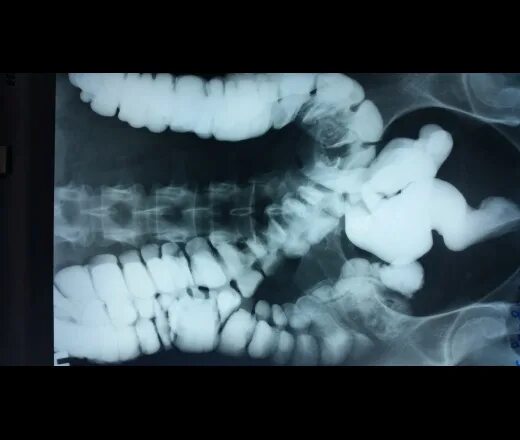

Ирригоскопия с двойным контрастированием